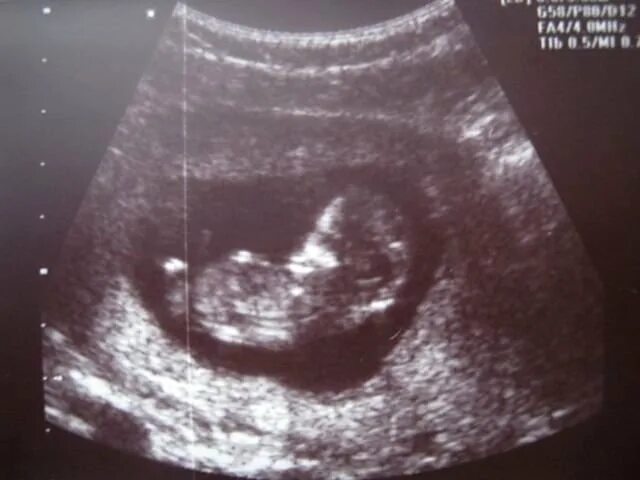

Ему было 11 недель